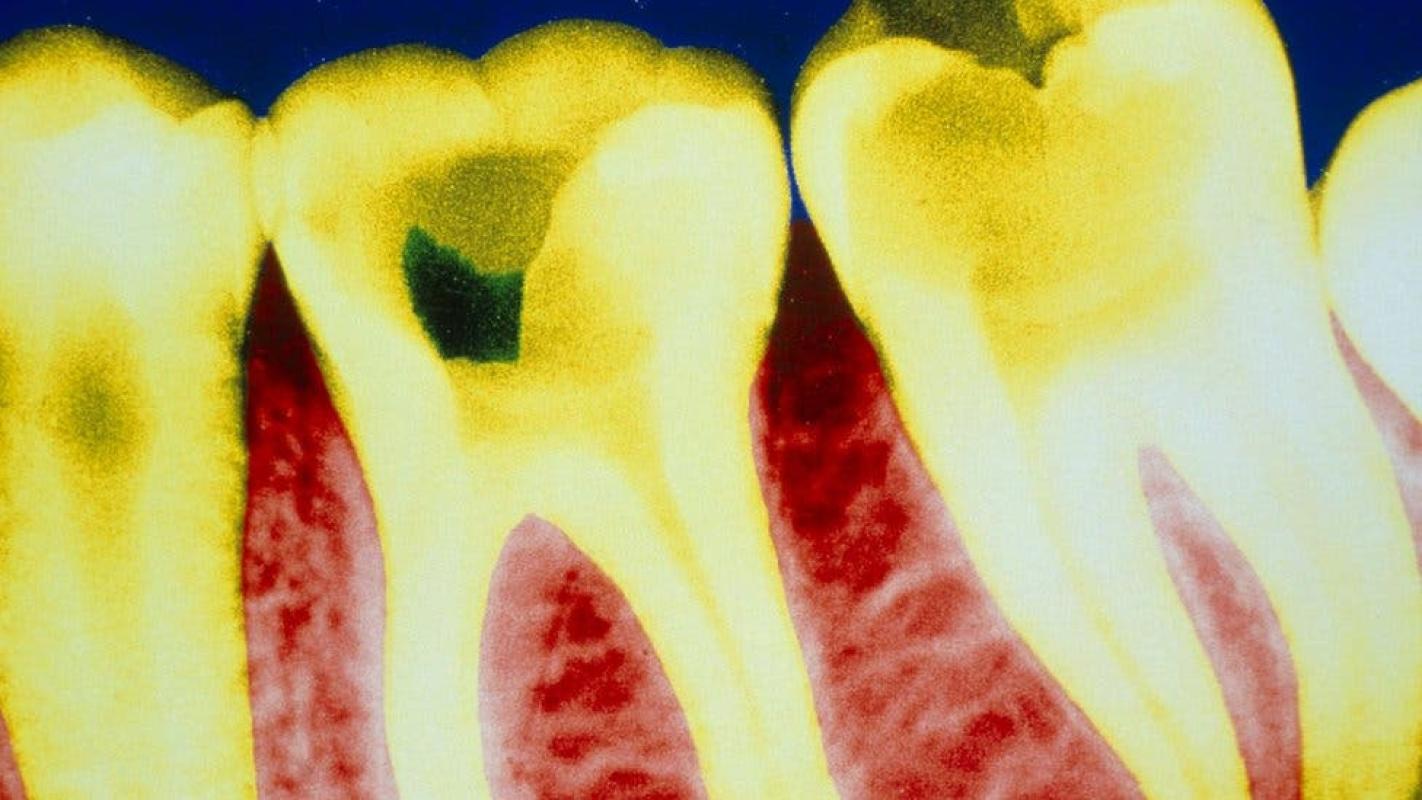

Lsa caries son la enfermedad dental más común en todo el mundo. Se caracteriza por la destrucción de los tejidos del diente y puede generar una inflamación del nervio dental que causa dolor.

Los dientes tienen naturalmente una cierta capacidad regenerativa: pueden producir una fina capa de dentina cuando la pulpa dental se queda expuesta.

La dentina, también llamada marfil o sustancia ebúrnea, es el tejido intermedio entre el esmalte dental, la capa externa más fuerte, y la pulpa, el tejido conectivo en el interior del diente.

Pero esa capacidad regenerativa natural es limitada: no puede reparar una gran cavidad.